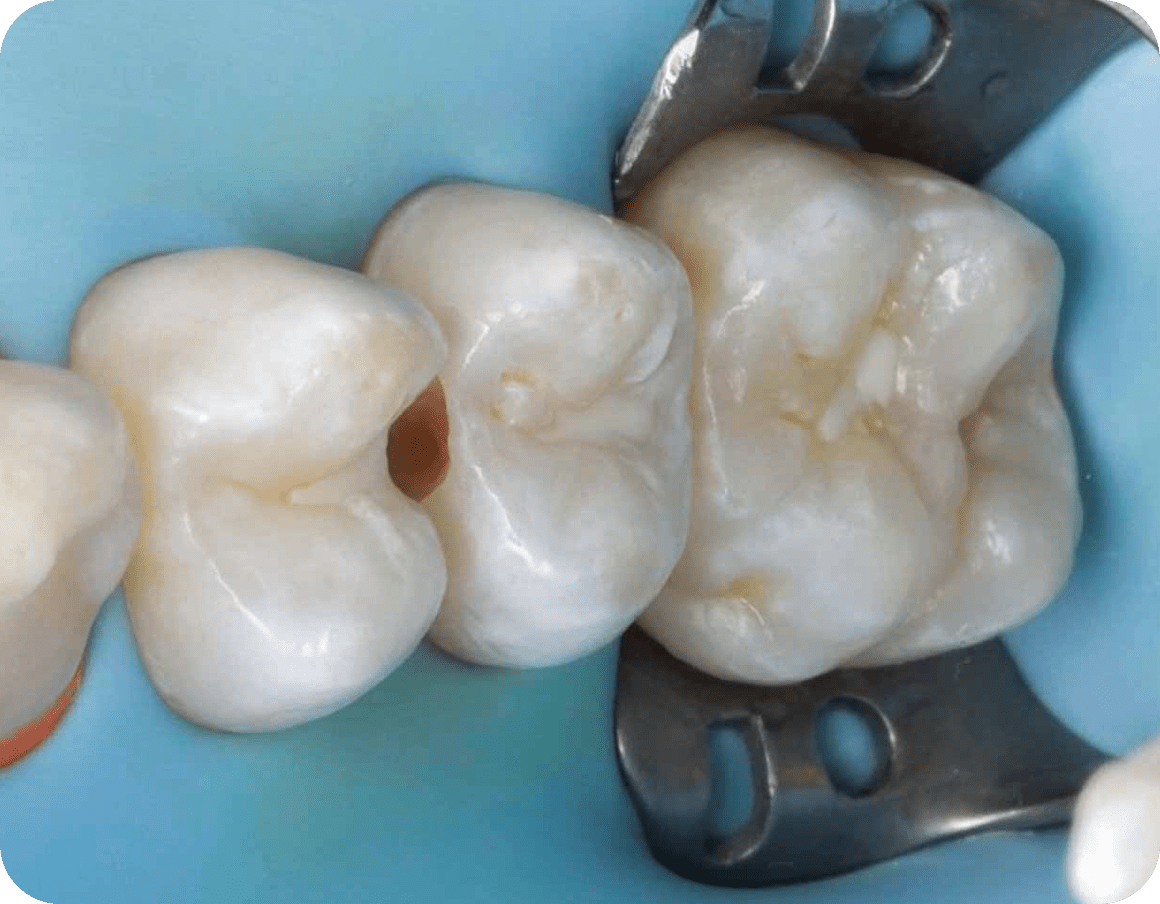

Коффердам – изолирующий платок

Латексный платок не дает протекать слюне во время установки пломбы

Это обеспечивает высокое качество приклейки пломбы к зубу